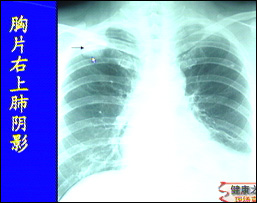

主持人:怎样才能知道自己是否得了肺癌? 王俊:最简单的方法就是到医院做一个体检,其中包括胸片检查,到目前为止胸部X线检查仍然是肺癌的首选筛选检查,如图这位病人在右肺上叶有一个小的结节,然后进行CT检查就是为了明确诊断和分期。近年来肺癌已经成为了人类肿瘤死亡的头号杀手。建议40岁以上有长期吸烟史的人最好每年进行一次体检,以便发现肺癌的早期病变,因为对于晚期肺癌目前医学界还没有很好的解决方法。

主持人:今天所介绍的微创治疗原理是什么? 王俊:从图中可以看出患者的右肺上叶有一个直径2厘米的病灶,可以在胸腔镜下切除掉这个病灶,切下的标本可以送病理检查,在半小时内就可以知道这个肿瘤是良性的还是恶性的。如果是肺癌,肺功能很差,采取这种姑息治疗就可以了,如果患者的肺功能很好,要达到根治治疗的目的就需要再进行根治手术,往往要加一个小的切口,在胸腔镜下就可以很顺利地完成。